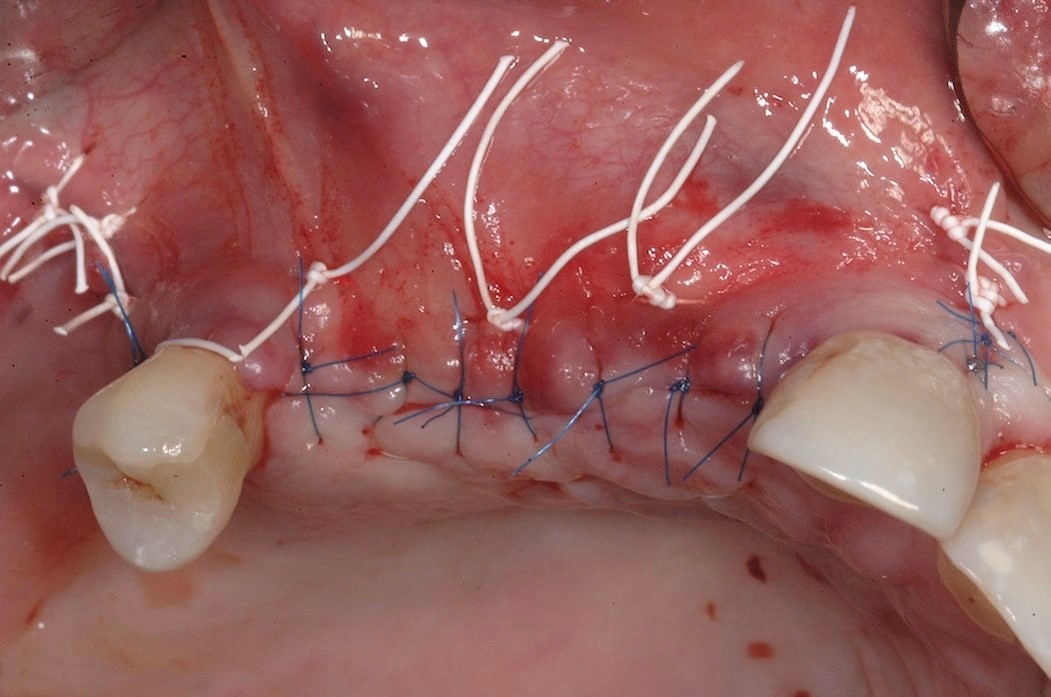

Fig 7. Three horizontal mattress sutures were placed, followed by a series of very thin, interrupted stitches.

Figure 7